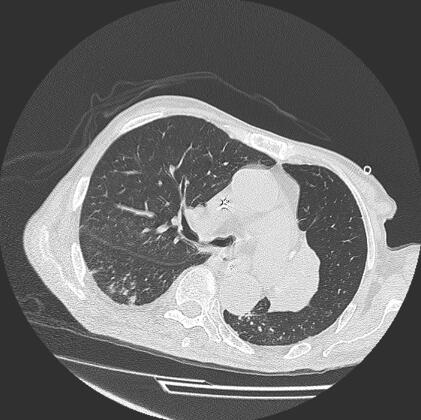

抗生素改用头孢哌酮-舒巴坦钠3g,每8小时1次,拔除深静脉导管。7月1日体温降至36.5℃,痰培养示鲍曼不动杆菌,药敏同前,管尖培养铜绿假单胞菌,血尿培养未见细菌生长,因患者体温不高,痰量减少,血压升至正常水平,继续应用头孢哌酮-舒巴坦钠,剂量3g,每12小时1次。7月3日、7日痰培养仍为鲍曼不动杆菌,未见铜绿假单胞菌,7月12日血、尿、痰培养未见细菌生长,降阶梯治疗,停用头孢哌酮-舒巴坦钠,改美洛西林钠-舒巴坦2.5g,每8小时1次,感染控制好,患者于7月20日带药出院。住院期间胸部X线片见图1~图6。部分化验结果对比见表1。

图5 2011年7月12日胸CT